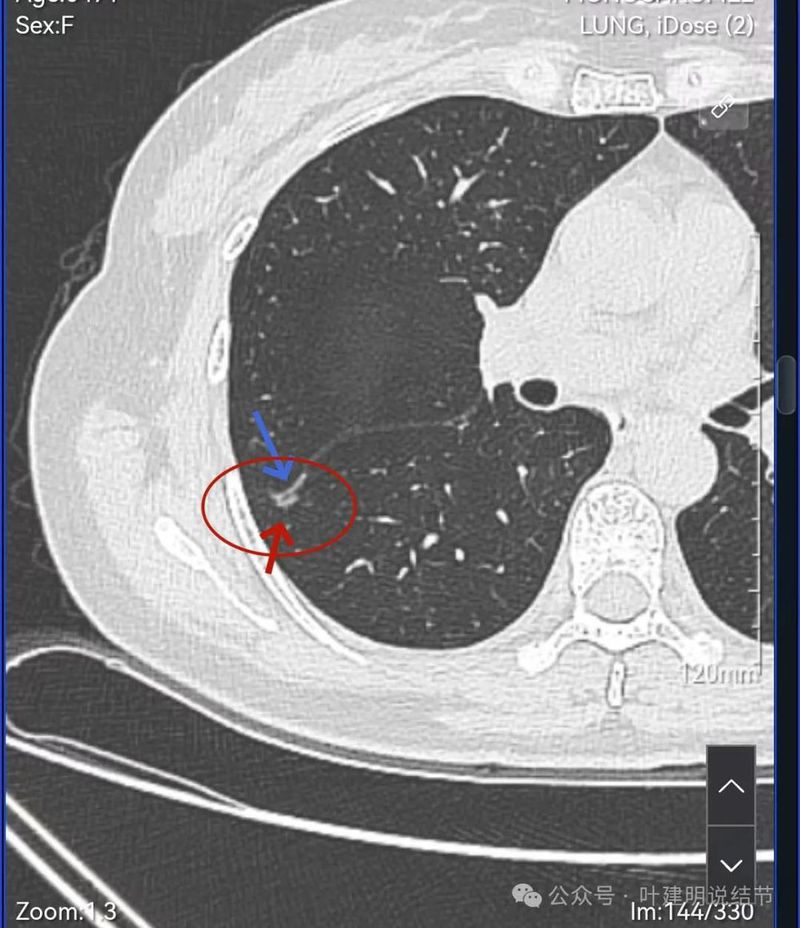

灶内血管穿行,表面分叶、中间空泡,实性成分。

血管进入,表面分叶,密度不均。